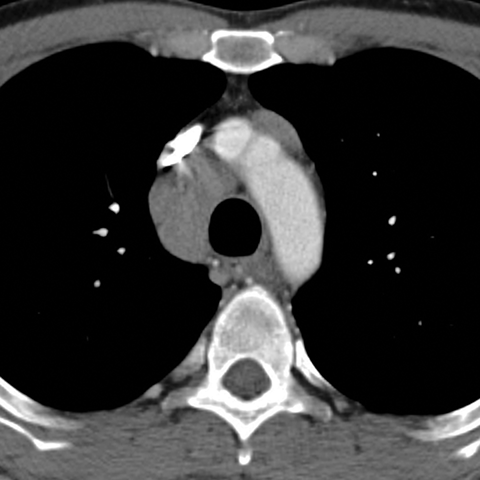

Mediastinal Lymph Nodes in NHL (Axial CT) [1 of 4]